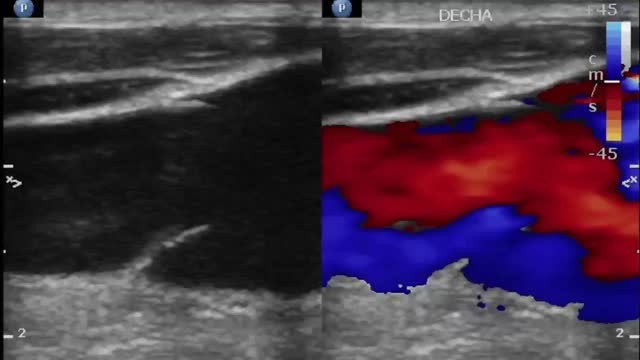

A 74-years-old man with a history of ascendant aortic dissection repaired 5 years ago and two mayor episodes of intrathoracic infection needing long-term antibiotic treatment, came to the ER for a presternal tumor. CT scan detected a preaortic mass suggestive of an aortic pseudoaneurysm. Surgery was planned but cancelled for mild respiratory infection, acute renal and hepatic failure, needing ICU admittance. In the ICU, the patient at physical exploration neck engorgement and pulsatility stood up (video 1). Vascular and cardiac bedside ultrasound showed a reversed systolic flow in the jugular veins (video 2) and a severe triscuspid regurgitation (video 3) secondary to pulmonary hypertension due to extrinsic compression of the psedoaneurysm over the pulmonary artery (white arrow in Fig. 1). The patient rejected aggressive treatment and passed away 2 days later.